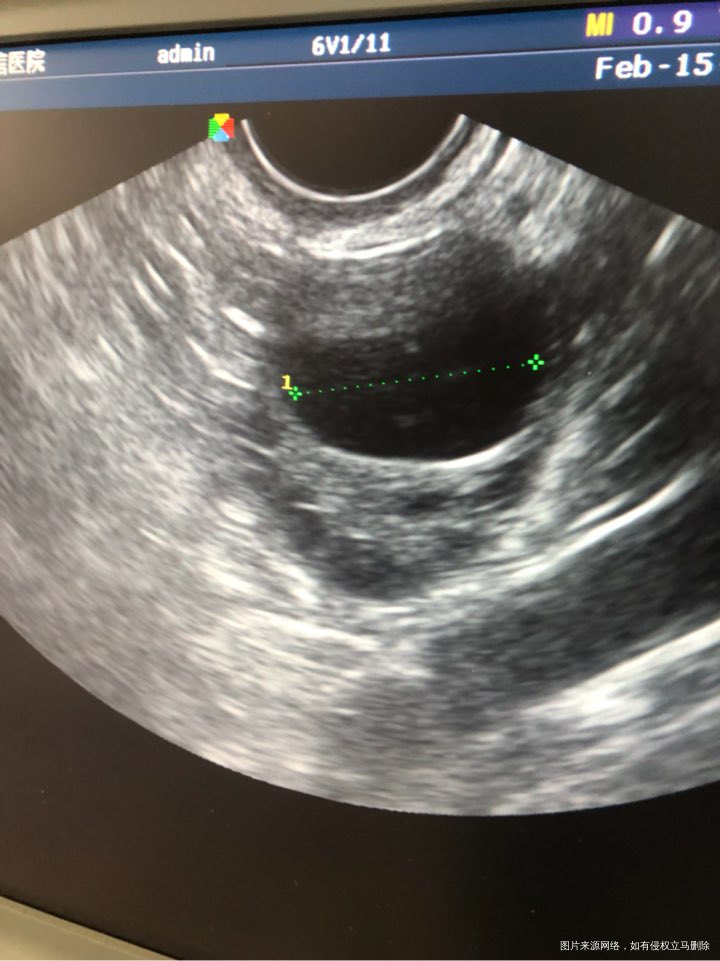

2月12日与2月13日分别打了两针150到位的尿促,今天内膜2.3乘1.5不圆,还不排卵,怎么办呢不圆是否有影响呢。

你好,根据你的描述具体建议如下:1 目前卵泡不圆,内膜0.75,这个不要太担心。因为卵泡一直发育,情绪紧张着急生气会影响卵泡发育哦。正常尿促就是促进卵泡发育的,促排是需要绒促哦。目前继续观察卵泡发育与内膜厚度。 2 正常成熟优势卵泡1.8--2.5之间,内膜0.8--1.0就要促排卵药物(绒促或加中成药止痛化癥或是丹黄祛瘀等等),配合适当活动比如跳绳,就可以成功排卵的。目前卵泡还在变化中,一定放松心情,饮食营养均衡搭配,按照医生的建议为准。 3 之后卵泡发育成熟排卵期,隔日同房就有好孕几率。祝健康。祝你好孕。如果我的建议对您有帮助,请记得选择点击采纳

卵泡已经成熟了,不圆也没事的,不能排出,可以今天肌注人绒毛膜促性腺激素10000u促进卵泡排出,明晚同房,隔天一次,可以排卵后10天化验血hcg,或排卵后14天早孕试纸测一下怀孕。祝好孕,孕前3个月至孕3个月口服叶酸预防胎儿脑神经畸形!如果我的回答对你有帮助,请采纳!谢谢

您好,卵泡不圆不影响受精的,卵泡已经成熟了,可以肌注人绒毛膜促性腺激素促进卵泡排出,明天继续监测直至监测到卵泡排出后安排同房,隔日一次受孕几率最大,排卵期同房后10天去医院抽血检查hcg确诊是否怀孕,如果血值大于10那恭喜你怀孕了,隔2-3天再复查看翻倍情况,翻倍好说明胚胎着床发育好,那就放心了,记着口服叶酸片至孕后满3个月预防胎儿脑神经畸形的,要注意休息不能劳累,加强营养饮食方面以清淡为主,多吃豆制品高蛋白的食物,不能吃辛辣油腻刺激性的食物,如果我的回答对你有帮助,请点采纳!谢谢你了!